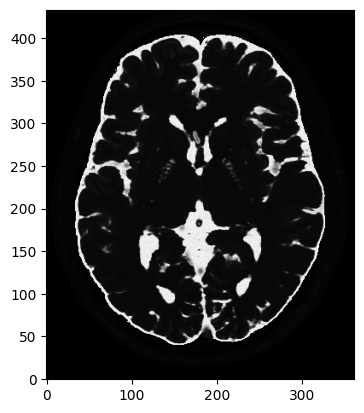

# T2 weighted image

mri_2D = bwdl.get_mri(4, "T2")[150, ...].astype(np.float32)

print(mri_2D.shape)

plt.figure()

plt.imshow(abs(mri_2D))

plt.show()(434, 362)